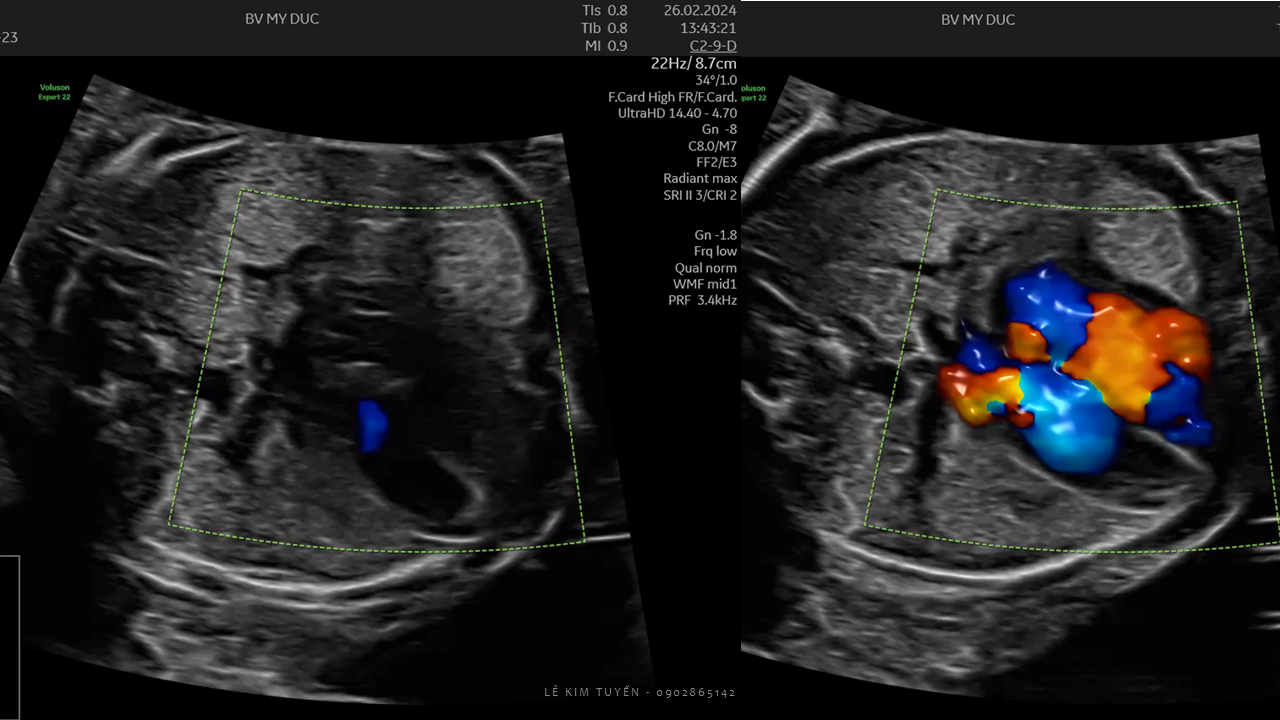

Siêu âm tim thai - Các kỹ thuật hiện đại

TS. BS. Lê Kim Tuyến

Bệnh viện Tim Tâm Đức